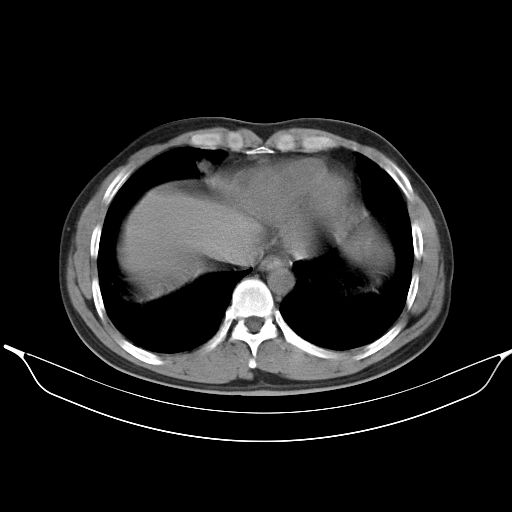

标题: CT25490:男,40岁,体检发现;无其它不适。 [打印本页]

标题: CT25490:男,40岁,体检发现;无其它不适。

考虑右下肺周围性肺癌并肺内多发转移,纵隔淋巴结转移!

支持 !考虑右下肺周围性肺癌并肺内多发转移,纵隔淋巴结转移,(气管前腔静脉后,隆突下,主动脉弓下都有了)

1、均为转移,原发灶不在肺内。2、肺癌肺转移。